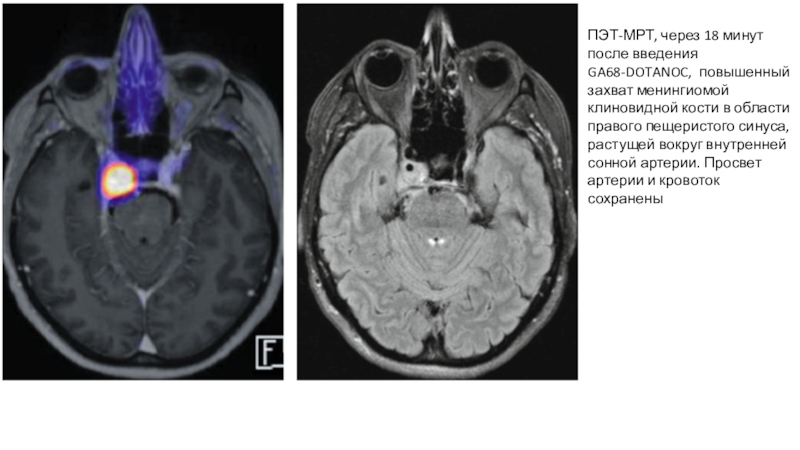

Слайд 20ПЭТ-МРТ, через 18 минут после введения GA68-DOTANOC, повышенный захват менингиомой

клиновидной кости в области правого пещеристого синуса, растущей вокруг внутренней

сонной артерии. Просвет артерии и кровоток сохранены

ПЭТ-МРТ, через 18 минут после введения GA68-DOTANOC, повышенный захват менингиомой клиновидной кости в области правого пещеристого синуса,